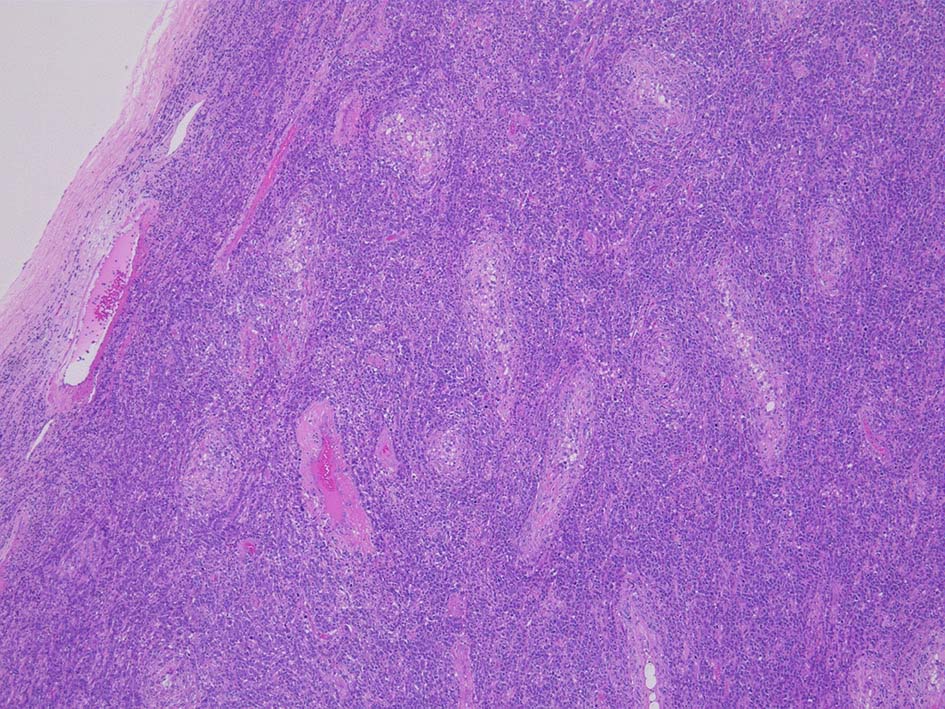

光顕所見; リンパ腫により, 少なくとも一部の領域の精細管が消失する. 末梢の領域では精細管の間質にリンパ腫細胞が浸潤する. ほとんどの場合、腫瘍細胞は精細管に侵入, 精細管の周辺を占め、生殖細胞とセルトリ細胞を中央に変位させるか, または精細管を完全に占拠してしまう.

腫瘍内に壊死が認められる. 異型リンパ球の密な増殖により精細管は消失している.

増殖巣では精細管は消失, 萎縮. 腫瘍境界部での浸潤所見がある.

精細管の多くがスペアされ, 間質にlymphoid cellsが密に浸潤している. わずかな精細管に浸潤が認められ萎縮や破壊像が認められる. 精細管において Lymphoepithelial lesion(LEL)に似た所見がある.